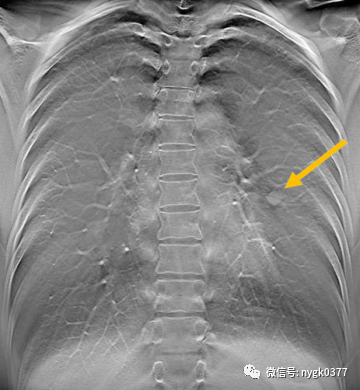

断层融合应用于胸部结节筛查:

岛津有哪些影像设备岛津 C200拥有性能完善的影像链系统_https://www.jmylbn.com_新闻资讯_第7张

胸部平片漏诊病例

岛津有哪些影像设备岛津 C200拥有性能完善的影像链系统_https://www.jmylbn.com_新闻资讯_第8张

断层融合清晰看到左肺叶结节